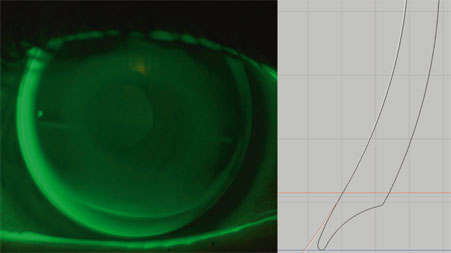

Fig. 4-12 Aberration optique créée volontairement dans la lentille, de manière à augmenter la profondeur de champ et la pseudo-accommodation.

Si la sensibilité aux contrastes valide la perte de sensibilité, l’aberrométrie permet d’en évaluer la cause. Fujikado et al., dans une étude réalisée en 2004 [20], ont montré que les aberrations de type coma et l’aberration sphérique augmentent significativement dès cinquante ans. Selon Amano et Fujikado [1], les aberrations de type coma liées à l’âge seraient dues aux aberrations de la surface antérieure de la cornée, alors que les aberrations sphériques seraient dues aux modifications du cristallin, notamment au cours de l’accommodation, et aux aberrations de la face postérieure de la cornée[1, 2, 20, 24, 39].

Une étude personnelle réalisée avec la collaboration de Damien Gatinel [37] a porté sur trente yeux de vingt-trois patients différents, de tous âges. La taille de la pupille a été un des éléments de l’étude, car l’amplitude des aberrations dépend de la taille de la pupille. Plus la pupille est grande, plus les aberrations de type coma et l’aberration sphérique sont importantes et vont entraîner une dégradation de l’image rétinienne. Des géométries multifocales à vision simultanée, à vision centrale de loin ou de près, utilisées en pratique courante, ont été testées sur chacun des trente yeux. Les résultats ont montré une augmentation systématique de la magnitude des aberrations optiques de haut degré. Les lentilles à vision de loin centrale vont accentuer les aberrations de sphéricité positives, les rayons périphériques étant plus convergents que les centraux. Ceci explique les halos importants ressentis en vision nocturne avec ces lentilles. À l’inverse, celles à vision de près centrale réduisent les aberrations positives. La genèse des aberrations impaires de type coma serait vraisemblablement en rapport avec un décentrement de la zone optique multifocale par rapport à la pupille d’entrée. Ceci corrobore l’étude de Château et al. [8] montrant un décentrement temporal inférieur dans plus de 70 % des cas.